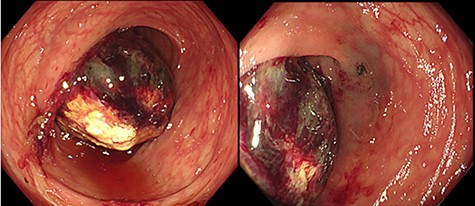

A 50-year-old woman visited a family hospital with complaints of left lower abdominal pain and bloody stool. She had no relevant past medical history or family history. She underwent colonoscopy, and a submucosal tumor was detected in her colon. She was referred to our hospital for further testing and treatment. Colonoscopy was performed, and an ulcerating submucosal tumor with necrosis at the surface was detected in the colon 40 cm from anal verge (Fig. 1). There were no other abnormal lesions in her colon. Histopathological examination of biopsy samples of the tumor comprised only exudate and no cellular components.

Colonoscopy findings: a submucosal tumor with ulceration and necrosis at the surface was detected in the colon 40 cm from anal verge. There were no other abnormal lesions in her colon.